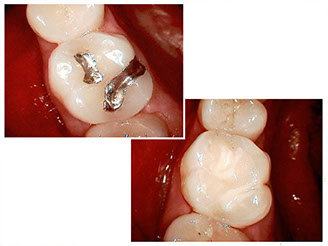

• Composite fillings

Composite, or white fillings, have been used in dentistry for several decades. This material involves an organic resin mixed with an inorganic filler to give it strength.

• Strong, durable, and bonds to tooth structure

• Seals the restoration and supports remaining tooth structure

• Requires removal of less tooth structure than previous materials